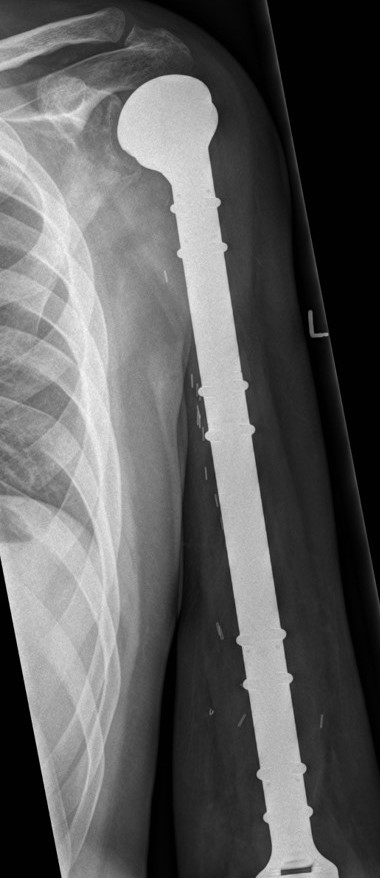

- proximal humerus 10%

Osteosarcoma of the humerus Osteosarcoma of the fibula

Post distal femoral osteosarcoma resection